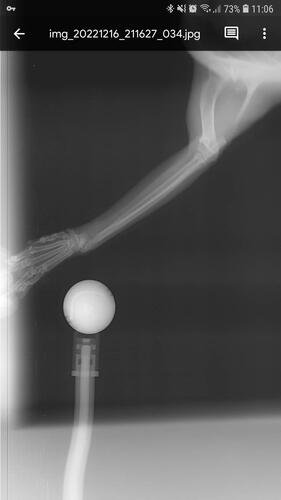

Depois de algumas consultas e até mesmo um diagnóstico errado, enfim descobriram que eu estava com as patinhas fraturadas, e pela forma como estavam a explicação era apenas uma: fui mais um alvo da maldade humana.

Eu preciso operar as patas o quanto antes, pois venho tendo perda óssea e mal consigo usar minha caixa de areia. Vivo apenas deitada e é minha mãe quem me alimenta e me da água na boca, além de levar na caixina, pois como podem ver nas fotos, minhas patas estão tortinhas e não consigo mais o mínimo de apoio.